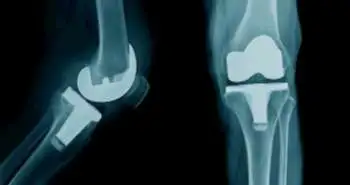

The severe pain and disability associated with osteoarthritis often motivate individuals to undergo arthroplastic surgery. However, a significant number of surgical patients continue to experience pain following surgery. Prior research has implicated both the hypothalamic-pituitary-adrenal (HPA) axis and sympathetic nervous system (SNS) in the sensitization of pain receptors and chronic pain conditions. This study uses a prospective, observational, cohort design to examine whether physiological stress responses before and after surgery could predict post-operative pain severity.

Participants included 110 patients undergoing total knee arthroplasty. Physiological indices of stress included the measurement of catecholamine and cortisol levels in 15-hour urine samples collected prior to and 1 month following surgery, as well as in-hospital heart rate and blood pressure (before and after surgery), which were abstracted from medical records. Patients completed the pain subscale of the Western Ontario and McMaster Universities Osteoarthritis Index (WOMAC) 2.5 weeks prior to surgery and at a 3-month follow-up.